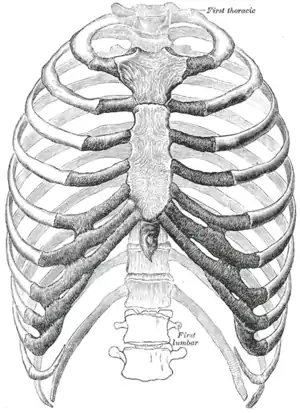

![]() Protection on the rib cage of the heart, lungs and diaphragm. The shaded areas indicate the extent of the pleural cavities not filled by the lungs. | |

Anterior surface of sternum and costal cartilages.